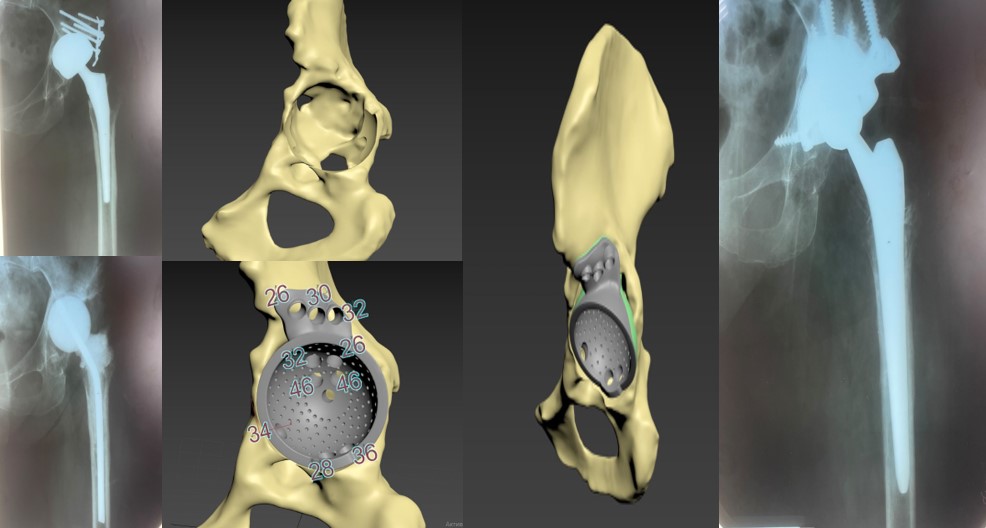

Приклад заміщення дефектів кісток тазу при ураженні пухлиною. Складне індивідуальне ендопротезування кульшового суглоба

Розрахунок розміру компонента, імплантація ревізійної ацетабулярної системи, Розмір трансплантованої кістки з використанням опорних площ, доповнюючи масивною кістковою пластикою дефектів з метою відновлення рекомендованої позиції компонента

Пацієнт С-к Роман Михайлович, 1975 рік. Травма в результаті ДТП (7.10.2023 р.) – перелом заднього краю лівої кульшової западини зі зміщенням. Післятравматичний лівобічний коксартроз 4 ст., стан після МОС заднього краю лівої кульшової западини пластиною та гвинтами. Згинально-привідна контрактура зліва. Наслідки ушкодження лівого сідничного нерва в лівій сідничній ділянці. Стан після встановлення ЕСС “НейСі-3М” на малогомілковий (CPN) та великогомілковий (TN) нерви в н/3 лівого стегна.

Операція: Вилучення металофіксаотора. Повна артропластика лівого кульшового суглоба з індивідуальним ацетабулярним компонентом

Пацієнт С-к Роман Михайлович, 1975 рік. Травма в результаті ДТП (7.10.2023 р.) – перелом заднього краю лівої кульшової западини зі зміщенням.

Післятравматичний лівобічний коксартроз 4 ст., стан після МОС заднього краю лівої кульшової западини пластиною та гвинтами. Згинально-привідна контрактура зліва. Наслідки ушкодження лівого сідничного нерва в лівій сідничній ділянці. Стан після встановлення ЕСС “НейСі-3М” на малогомілковий (CPN) та великогомілковий (TN) нерви в н/3 лівого стегна.

Спроектована та імплантована індивідуальна, пориста, титанова, 3D-друкована кульшова западина, фіксована гвинтами.